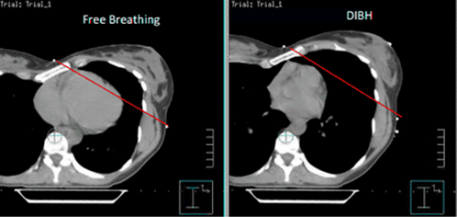

Deep inspiration breath hold technique (DIBH)

Using DIBH can help to limit the radiation that your heart and lungs are exposed to. The technique involves holding your breath for approximately 20 seconds at a time while your radiotherapy is being delivered (with normal breathing breaks in between treatment beams). The action of holding in a deep breath of air allows your lungs to expand and push your heart away from the treatment area.

Here at UHS it is used to treat left-sided breast cancer but can also be used for those with certain thoracic and abdominal cancers.